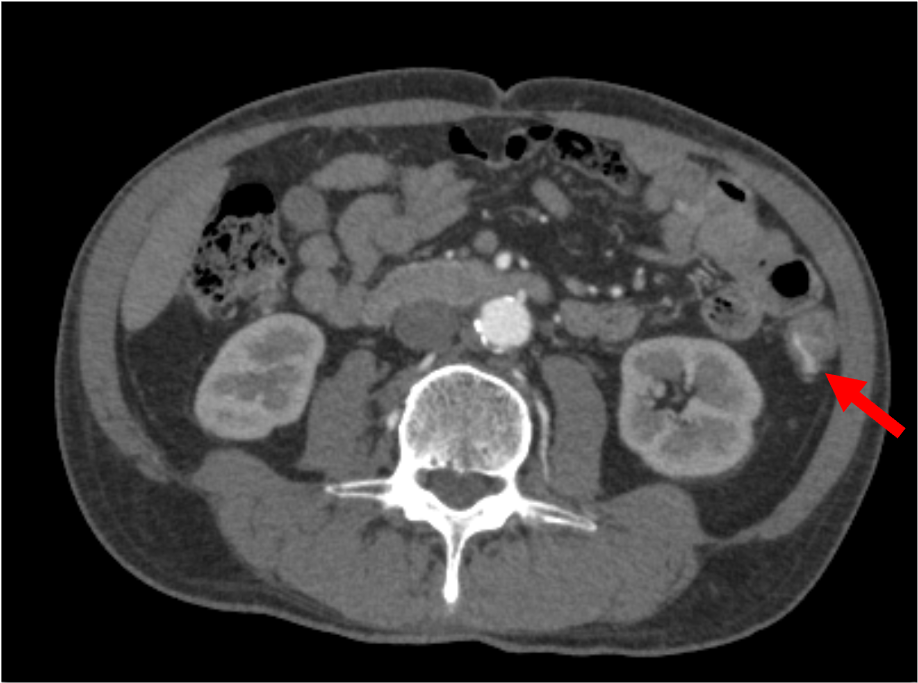

数日来の血便あり。臨床的に憩室出血が疑われCT検査が施行された。造影CTにて、下行結腸の憩室より造影剤の漏出像を認め、活動性出血と考えられた。下部消化管内視鏡でも下行結腸の憩室より噴出性の出血が確認され、憩室出血の診断。クリップにて止血処置を行い、止血が確認された。

当該疾患の診断における造影CTの役割